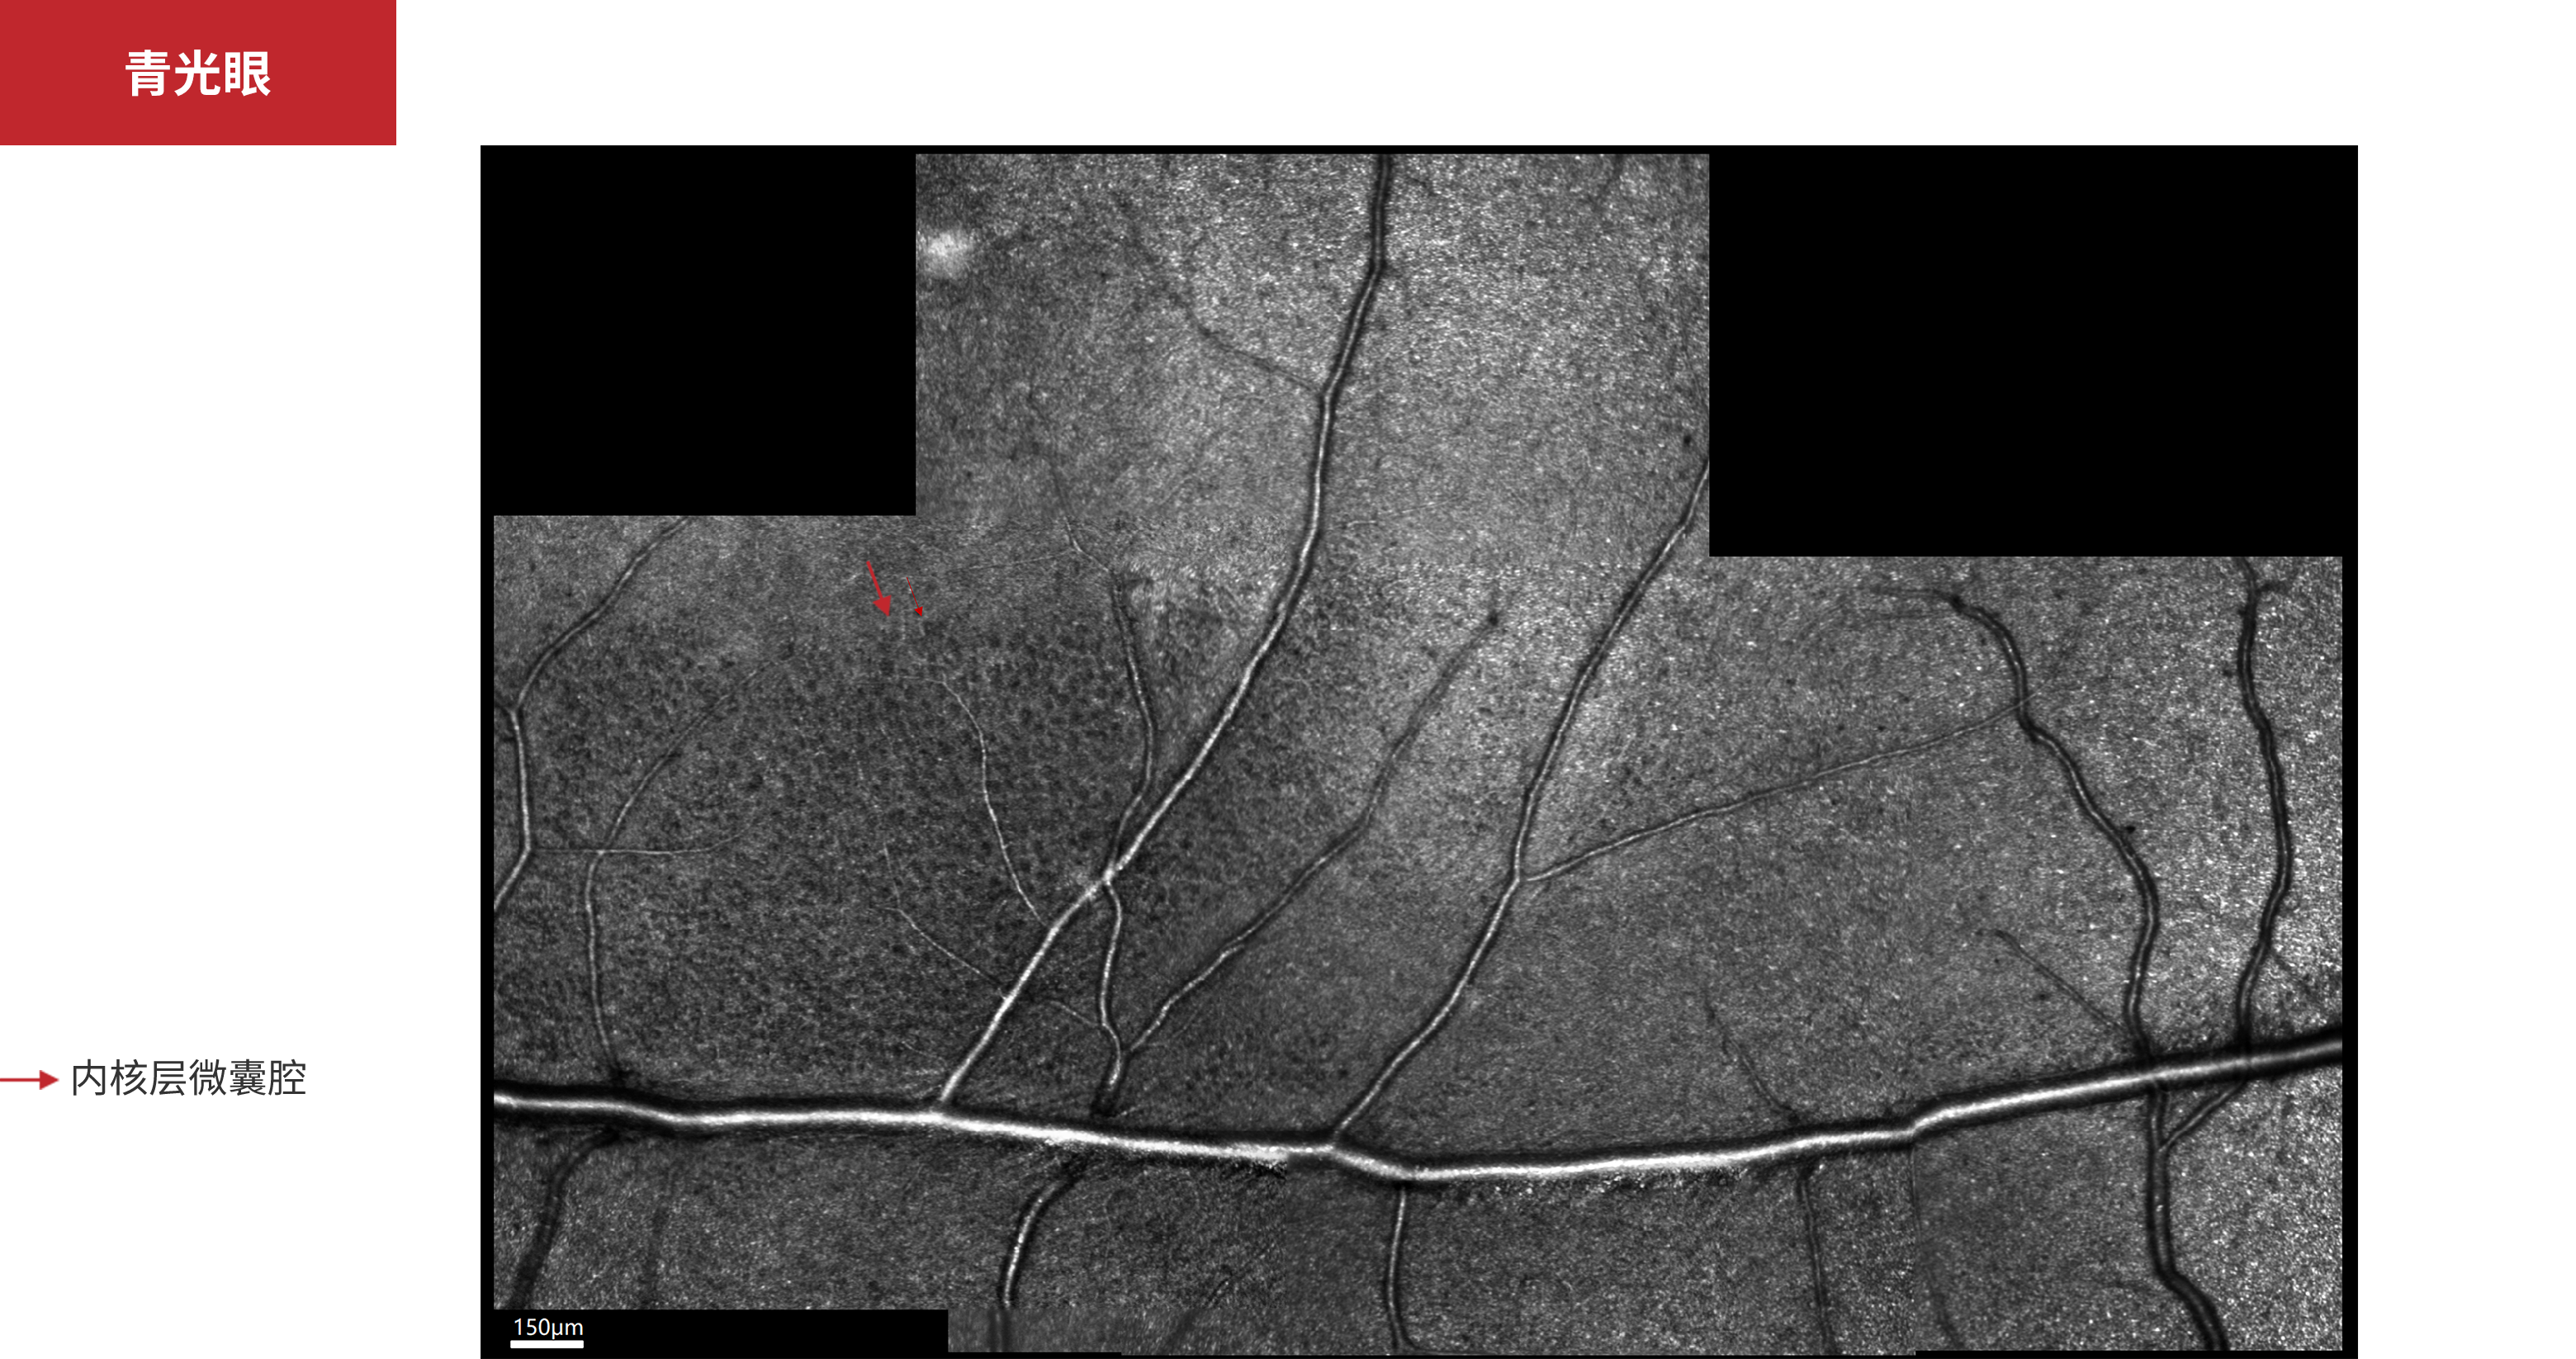

青光眼